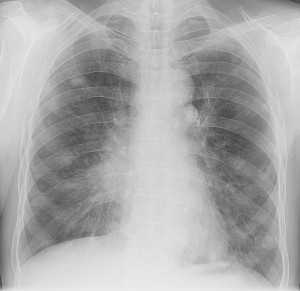

Гематогенные метастазы саркомы мягких тканей бедра на КТ (справа) и рентгенограмме (слева).